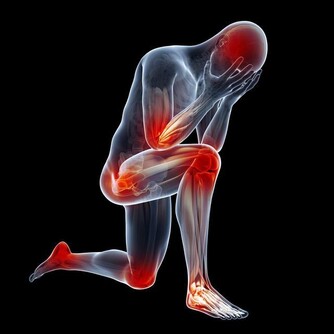

人體50%的骨骼和肌肉都在兩條腿上,人一生中70%的活動和能量消耗都要由它完成;

兩條腿上有人體50%的神經及血管,流淌著50%的血液,是連接身體的大循環組織。

■腿部衰老的8大預警信號

1、腿腳沒有以前靈便了,稍多走點路,就會發酸發脹。

2、用點力或者站的時間稍長,就會腰酸腿疼。

3、步速越來越慢,偶爾走快點,會覺得腿腳不聽使喚。

4、 即使是夏天,也經常會感到小腿肚涼颼颼的,有時還會從臀部一直涼到腳後跟。

5、 抽筋次數增多。

6、雙腿腫脹。

7、 靜脈曲張,腿部血管非常清晰。

8、髖膝關節疼痛,甚至有摩擦磨損、卡住動不了的感覺。